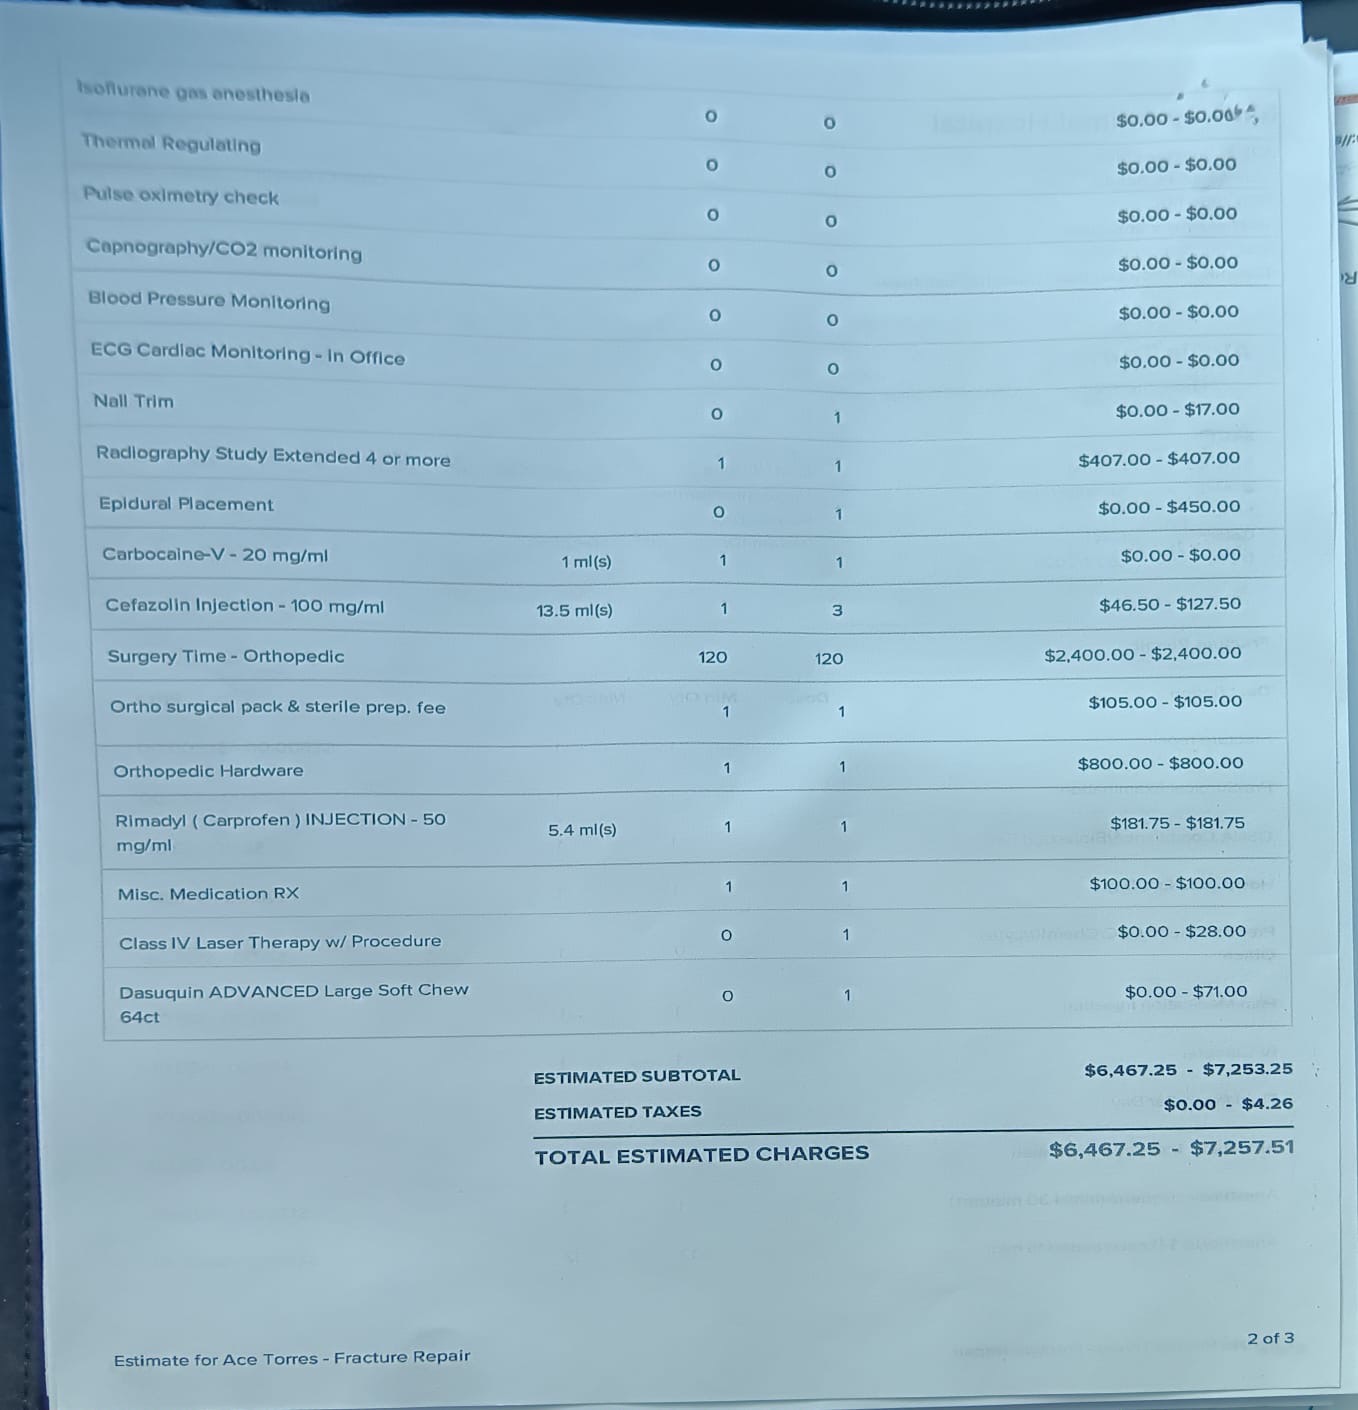

The funds raised will go directly toward Ace’s surgery and the medical care he needs to recover. This support will help cover the costs of his operation, medications, and follow-up treatments, giving Ace the best possible chance to heal and return to the happy, loving life he shares with us. We are doing everything we can, but we can’t do it alone.